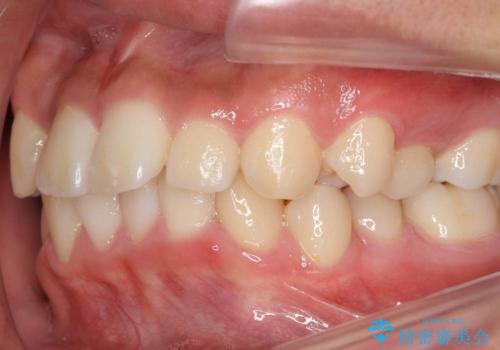

抜歯矯正の長期予後(術後8年目)

- ワイヤー矯正による治療後7年以上経過した患者様です。当時上の小臼歯を2本抜歯しています。

10代で矯正治療を行い、現在20代になられています。

矯正後8年目になりますが、並びも綺麗に保持でき、また上下の歯がさらにしっかり咬んできているのがわかります。

定期的にメンテナンスにきていただき、特に歯の健康状態にも問題がありません。

下は歯につけるタイプのワイヤーを貼っています。

上は取り外し式の装置を就寝時使っていただいています。